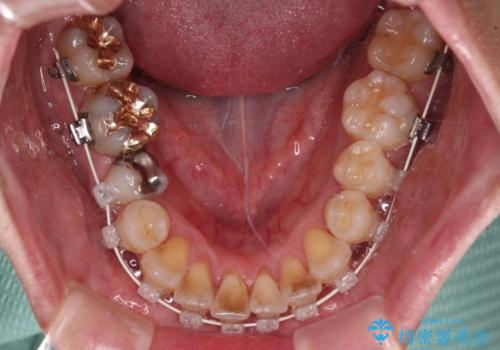

前歯のクロスバイト 目立たないワイヤー装置で矯正治療

- 審美装置

マウスピース矯正では前歯の神経への負担が大きいことを懸念され、ワイヤー装置による矯正治療を行うこととしました。

舌の突出癖の影響か、下顎前歯がなかなか整わず、治療期間は予定よりも長期間となりました。

舌突出癖改善のトレーニングの重要性を認識することとなりました。